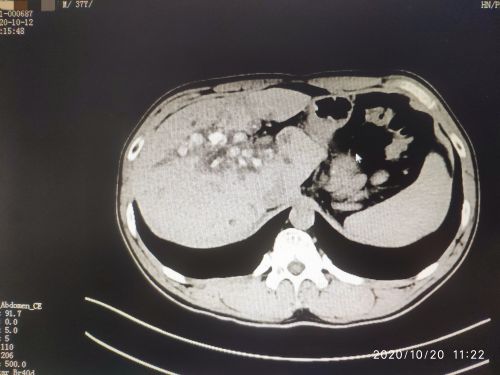

术前ct示肝内胆管结石分布。